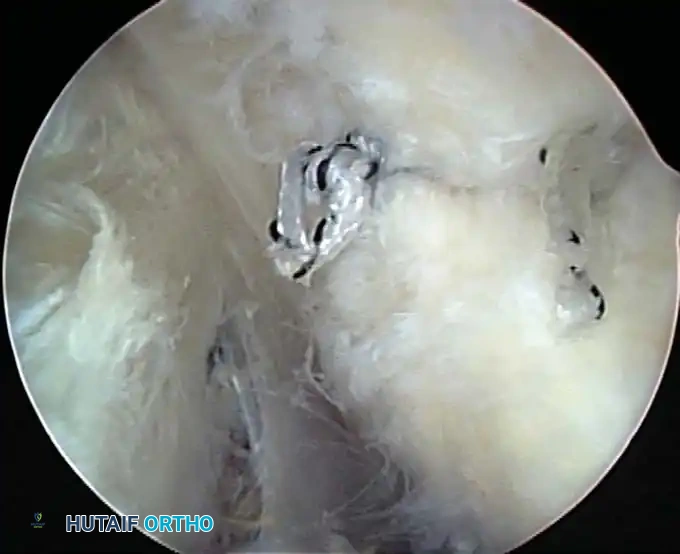

Once diagnostic evaluation is complete and hemostasis is secured, the therapeutic phase commences. Whether performing a SLAP repair, a Bankart stabilization, or a rotator cuff repair, the principles of tissue mobilization, anatomical footprint restoration, and secure biomechanical fixation remain paramount.

Modern arthroscopy relies heavily on suture anchors (biocomposite or all-suture constructs) and advanced arthroscopic knot-tying or knotless techniques. The ability to pass sutures through retracted, fibrotic tissue and secure them under appropriate tension without strangulating the microvascular supply is the hallmark of a master arthroscopist.